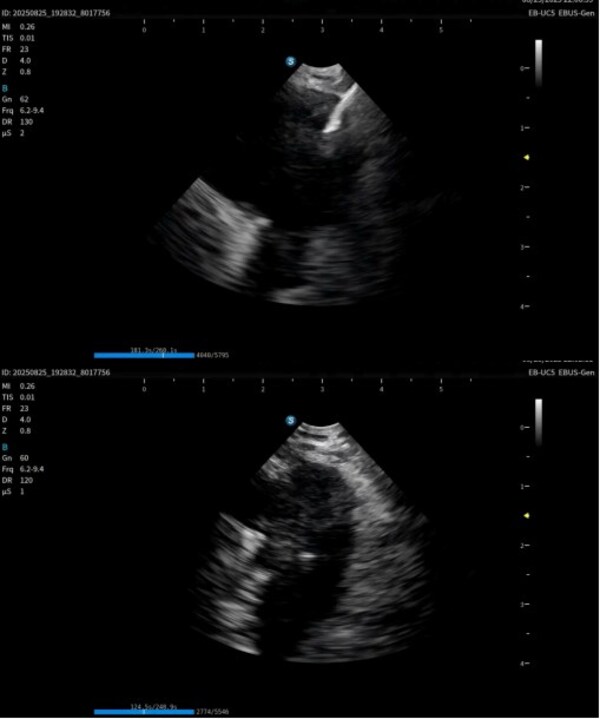

作為在呼吸診療領(lǐng)域的重磅產(chǎn)品,本次在產(chǎn)品創(chuàng)新設(shè)計上和工藝技術(shù)上取得了重大突破,顯著提升了光學(xué)圖像和超聲圖像的質(zhì)量,同時鏡體保持了良好的操作性,在鉗鏡比和視野角綜合參數(shù)可達到全球同類產(chǎn)品最佳性能。目前在臨床應(yīng)用表現(xiàn)突出,取得了專家的認(rèn)可和好評。

超聲電子支氣管內(nèi)窺鏡憑借其"微創(chuàng)、精準(zhǔn)、安全"的特點,已成為呼吸介入領(lǐng)域的核心技術(shù)之一。開立醫(yī)療全系列產(chǎn)品全面上市可為肺部腫瘤、縱隔病變提供管內(nèi)清晰光學(xué)影像,管外高清聲學(xué)斷層組織及血流影像,提供精準(zhǔn)可視化介入操作,為疾病的診斷提供更精準(zhǔn)、更安全、更高效的一體化診療解決方案。